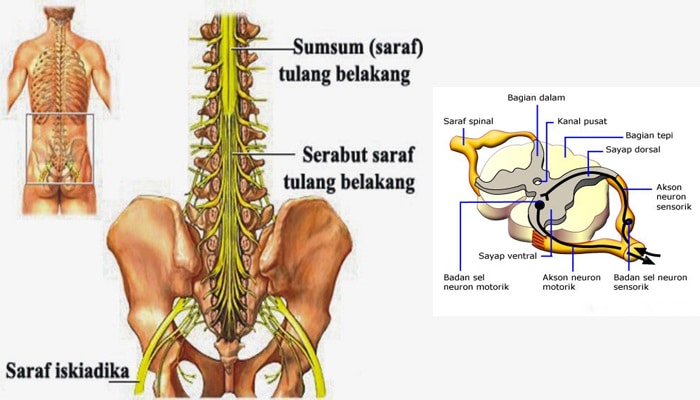

Sistem Saraf Pada Manusia Sistem Saraf Pusat Sistem

Sistem Saraf Pada Manusia Sistem Saraf Pusat Sistem